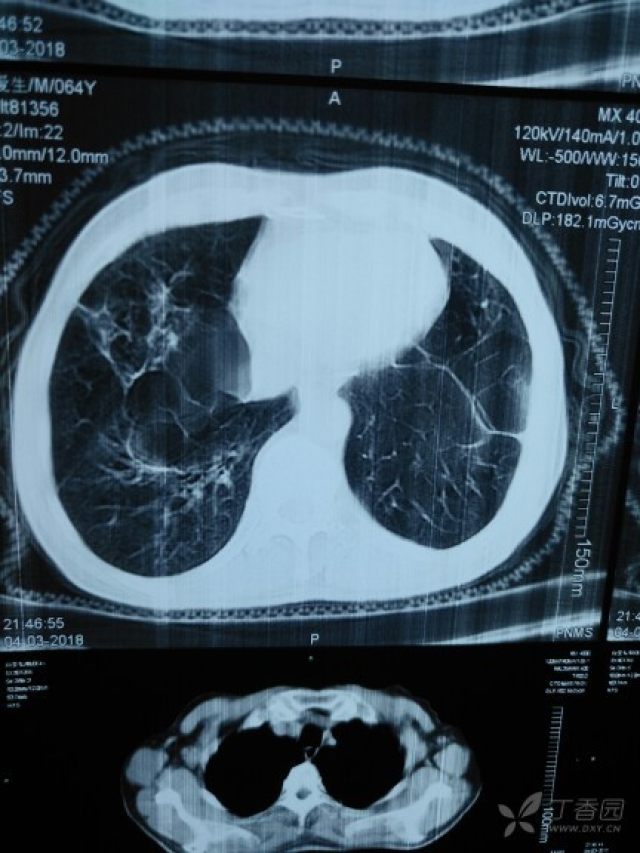

肺大泡 片子,肺大泡ct肺大疱

照片名称:左上肺肺大泡

还是肺大泡?

ct43400肺大泡支扩诚恳讨论鉴定

肺大泡

肺大泡ct肺大疱

肺大泡ct图片

肺大泡ct

肺大泡ct影像

肺大泡ct影像图片

肺大泡影像学表现图片

肺大泡在ct上的图像